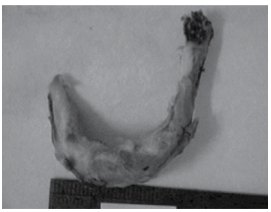

A figura seguinte representa osso hioide fraturado em vítima de suicídio por enforcamento.

Além do osso hioide, outras estruturas comumente passíveis de lesão nas asfixias por contricção do pescoço são: